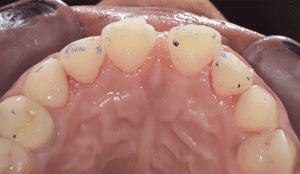

Dans notre cas clinique, il n’y avait pas de modification de la gencive à prévoir. Le mock-up est donc relativement réaliste. La patiente valide le diastème médian et le décalage des milieux (Fig.4).

Fig.4 : Essayage du mock-up.

Elle se rend compte que pour avoir ce sourire, il faut surélever en postérieur. La patiente valide le plan de traitement. Avec le mock-up en bouche, on enregistre avec de la résine d’occlusion (ici LuxaBite, DMG) l’espace d’inocclusion postérieur (Fig.5) en réalisant deux clés (une droite et une gauche). Cela permet d’avoir une stabilité dans le repositionnement des arcades lors des prochains enregistrements numériques.